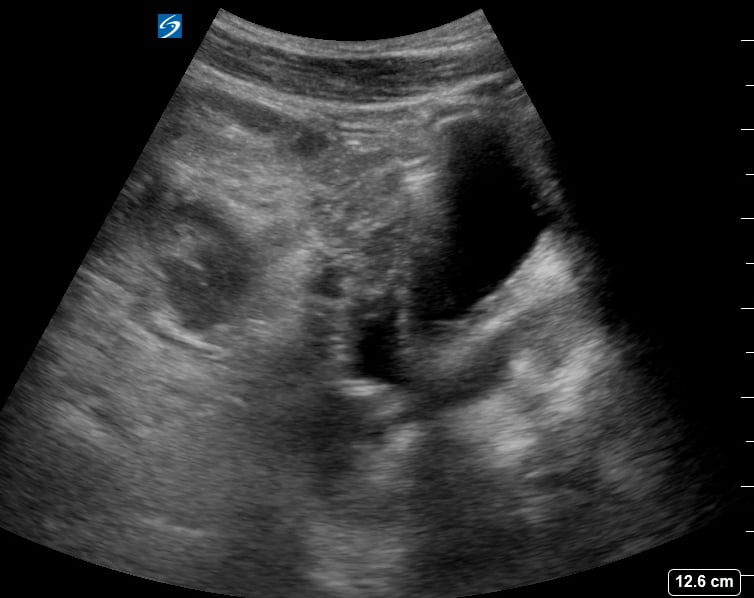

An ovarian cyst is a fluid-filled sac that develops on or within an ovary. Common in OBGYN, most ovarian cysts are benign and resolve spontaneously, but some may cause symptoms like pelvic pain or pressure, or indicate underlying conditions like polycystic ovary syndrome (PCOS). Ultrasound is the primary imaging modality for detecting and characterizing these cysts, providing crucial details on their size, shape, and internal features.

Accurate ultrasound assessment is vital for differentiating simple cysts from more complex or suspicious masses, guiding appropriate medical management and follow-up in gynecological practice. Early detection and precise characterization through medical ultrasound enhance diagnostic accuracy and optimize patient care.